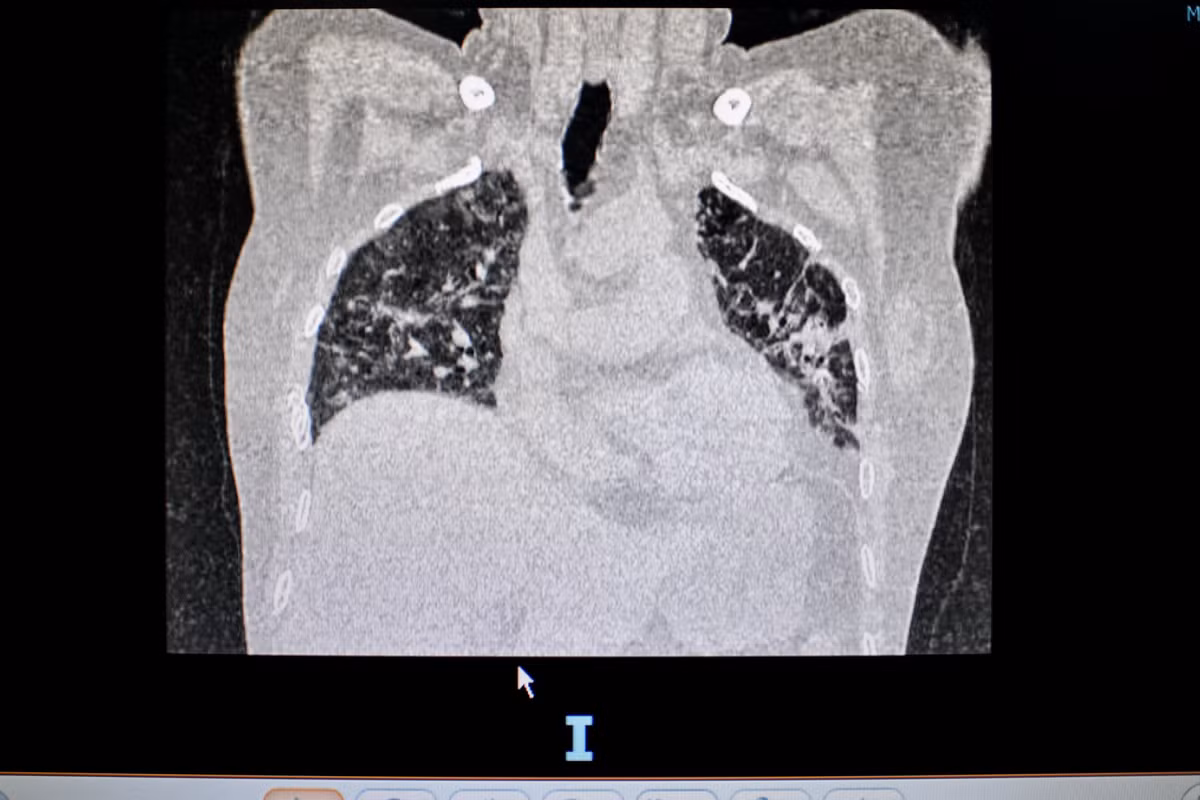

Bác sĩ Nguyễn Hải Công kiểm tra phim chụp phổi của một bệnh nhân điều trị di chứng hậu COVID-19. Ảnh: Bích Huệ.

Trên phim chụp phổi cắt lớp vi tính, các bác sĩ phát hiện người đàn ông bị tổn thương phổi dạng xơ hóa, giãn phế quản. Đây là di chứng vĩnh viễn, dù điều trị nhưng khó trở về bình thường.

Phim X-quang phổi của bệnh nhân 52 tuổi, bị suy hô hấp nặng sau khi khỏi COVID-19. Ảnh: Duy Hiệu.

Mới đây nhất, một phụ nữ 52 tuổi đến khám trong tình trạng suy hô hấp mạn tính, phải mang theo bình oxy dù khỏi COVID-19 gần một tháng. Trên phim X-quang, hai bên phổi của bệnh nhân mờ đục, diện tích tổn thương nhiều.